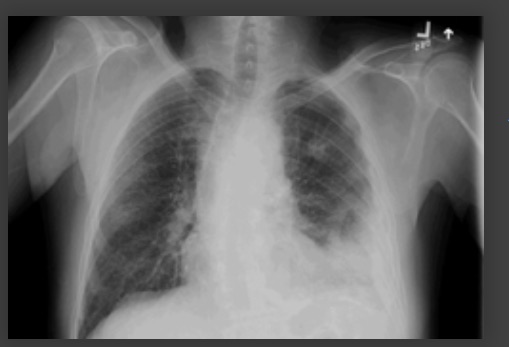

Considere una exploración tomografía computarizada (TC) de tórax si la radiografía es de mala calidad o si hay una consolidación mal definida.[1]

Considere una exploración por TC de tórax u otras pruebas diagnósticas mediante estudios por imágenes para detectar neumonía "complicada" o cambios atípicos en una radiografía de tórax, como cavitación, patrón de consolidación multifocal o derrame pleural.[89][Figure caption and citation for the preceding image starts]: Radiografía de tórax que muestra neumonía cavitante en el lóbulo superior izquierdoDe la colección del Dr. Jonathan Bennett. Usado con autorización [Citation ends].